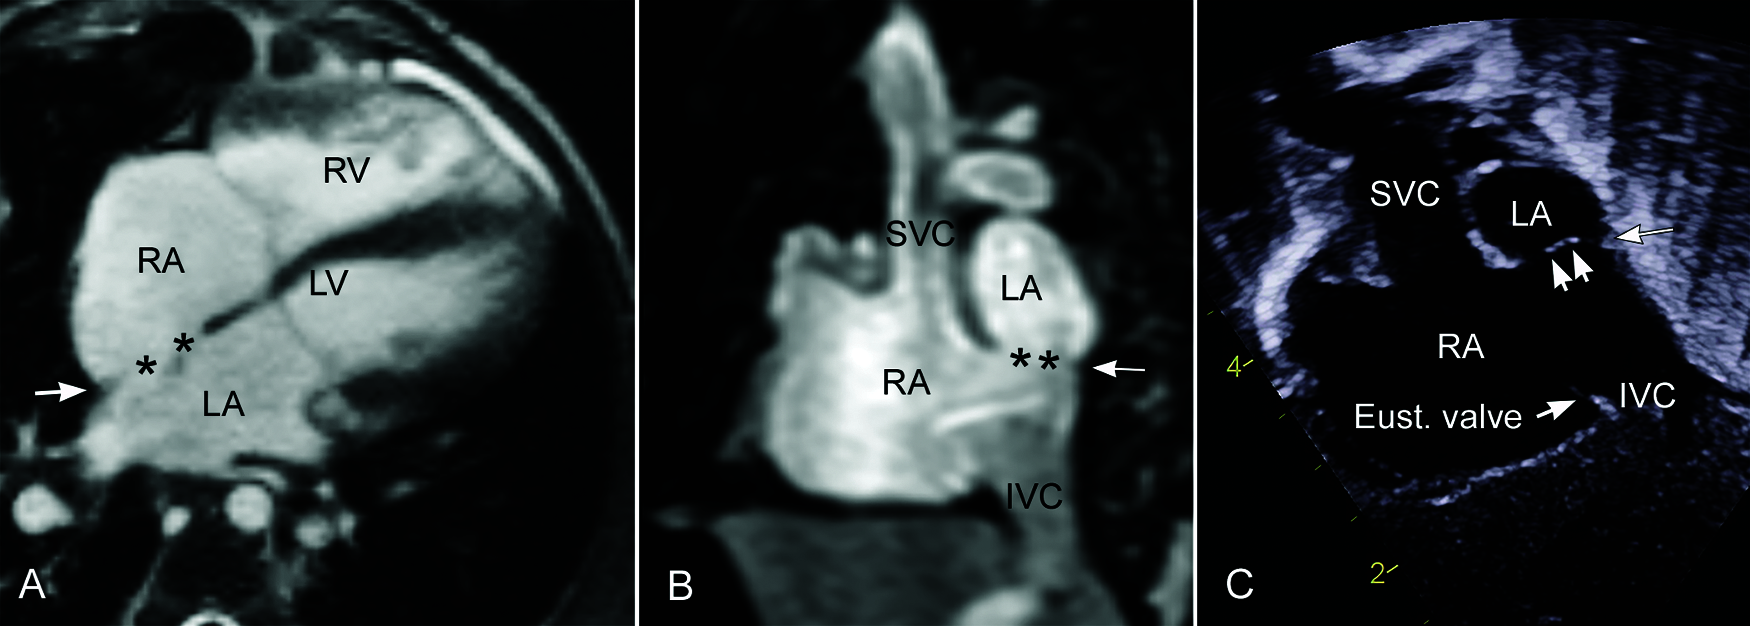

The inferior sinus venosus defect affects the lowermost convex part of the interatrial party wall along the sinus venarum. Invariably, the inferior vena cava appears to connect to the left atrium or override the defective atrial septum above. One may speculate malalignment of the atrial septum or malposition of the inferior vena cava as the underlying mechanism for overriding of the inferior vena cava. However, the position of the inferior vena cava and the orientation of the intact part of the atrial septum are not different from those of normal hearts. Overriding of the inferior vena caval orifice is due to the presence of a hole in the interatrial party wall that is normally in the trajectory of the course of the inferior vena cava (Fig. 6). A hole in the sloping posterior inferior part of the interatrial party wall simply lets the vena cava appear to connect to the left atrium especially when the Eustachian valve is prominent (Figs. 11 and 12).

Figure 12: Endocardial surface reconstruction of magnetic resonance angiograms from the same patient shown in Fig. 11B, showing the inferior sinus venosus defect. The right anterior wall of the right atrium and ventricle is removed. A is to show the relationship between the fossa ovalis (FO), limbus, coronary sinus ostium (CS) and Eustachian valve (Eust. valve) of the inferior vena cava (IVC). B and C are to show the orifices of the right middle and lower pulmonary veins (RMPV and RLPV, respectively) in relation to the defect and the atrial cavities. A large defect involves the far posterior inferior aspect of the interatrial party wall. The right middle and lower pulmonary veins connect to the lower part of the atrial cavity above the orifice of the inferior vena cava. SVC, superior vena cava

Inferior sinus venosus defects are frequently associated with anomalous connection of the right lower pulmonary vein to the right atrium or inferior vena cavoatrial junction. Some investigators consider the anomalous pulmonary venous connection to be an essential feature of the pathology [25]. However, the inferior sinus venosus defect often occurs with all pulmonary veins normally connected to the left atrium (Fig. 11A) [8,21,26–29]. Therefore, the presence of anomalous pulmonary venous connection to the inferior vena cava or right atrium is not essential for the diagnosis of the inferior sinus venosus defect. Interestingly, inferior sinus venosus defects also may be associated with anomalous connection of the right upper pulmonary vein to the right atrium [30].

In summary, the inferior sinus venosus defect is a congenital malformation that primarily affects the junctional area between the inferior vena cava and the lower part of the sinus venarum. Although frequently associated with an abnormality of the right pulmonary veins, this is not a constant feature required for the diagnosis of an inferior sinus venosus defect. The inferior vena cava appears to override the defective interatrial party wall or septum above or may appear to drain to the left atrium in almost all cases. Importantly, however, this finding is not due to abnormal position or orientation of the inferior vena cava or atrial septum but rather due to the unique alignment of the affected area of the interatrial party wall to the trajectory of the inferior vena cava.

As sinus venosus defects involve the most posterior aspect of the interatrial party wall, the defects are characterized by the absence of a posterior atrial rim along the free wall of the atrium in axial or short axis planes [8,27–29], which is described as “bald” posterior atrial wall (Figs. 11A–b and 11B–b) [28]. Precise unequivocal localization of the superior sinus venosus defect can be made using a parasagittal imaging plane along the sinus venarum, i.e., the parasternal intercaval or bicaval view [21,29,41–43]. The parasternal intercaval view is also a diagnostic plane for the inferior sinus venosus defect. However, a defect involving the most posterior and inferior part of the fossa ovalis can also be seen in this plane (Figs. 8C, 14 and 15) but without bald posterior atrial wall. Remnant of the attenuated limbus is seen as a small spur-like projection from the posterior atrial wall. As the limbus of the fossa ovalis is normally indistinct inferiorly toward the inferior vena caval orifice, the differentiation of the low lying secundum defect and the true inferior sinus venosus defect can be difficult at surgical inspection as well as at imaging.